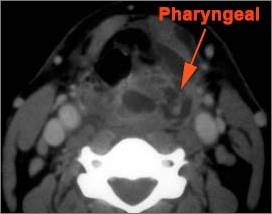

Oropharynx

There is excessive enhancement or thickening of the mucosa or hypertrophy of the palatine or lingual tonsillar tissue or the lymphoid tissue along the glossotonsillar sulci and posterior pharyngeal wall.